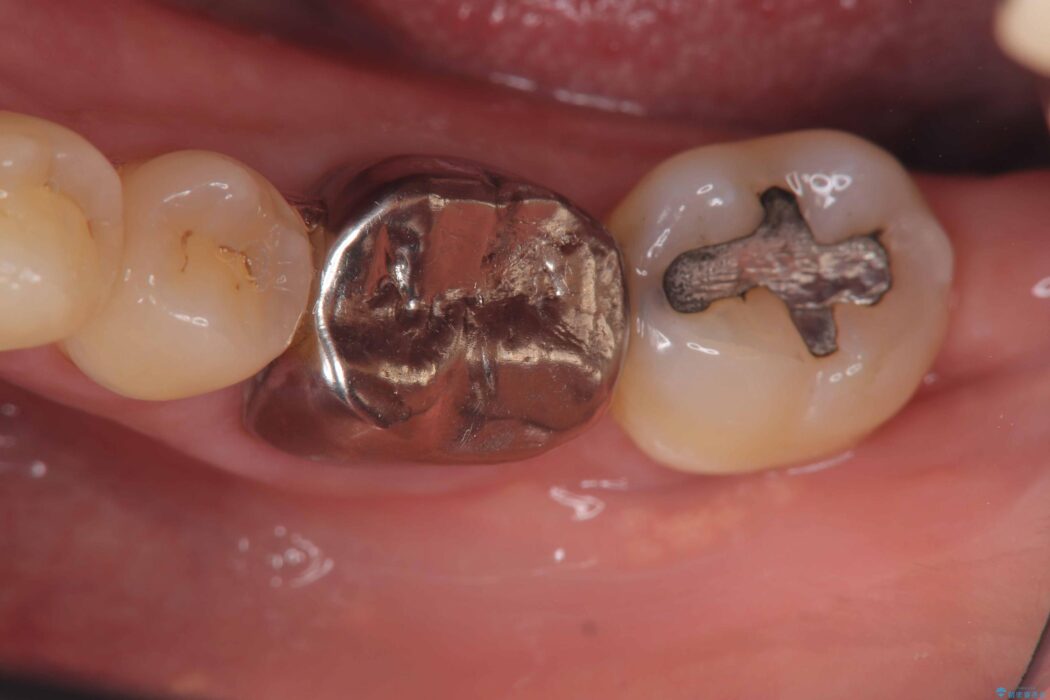

レントゲン検査にて、根尖および側枝付近に骨の透過像が認められました。

さらに精査したところ、根のパーフォレーション(根に穴が開いてしまっている状態)が確認されたため、

患者様と相談のうえ、インプラントにて治療を行うこととしました。